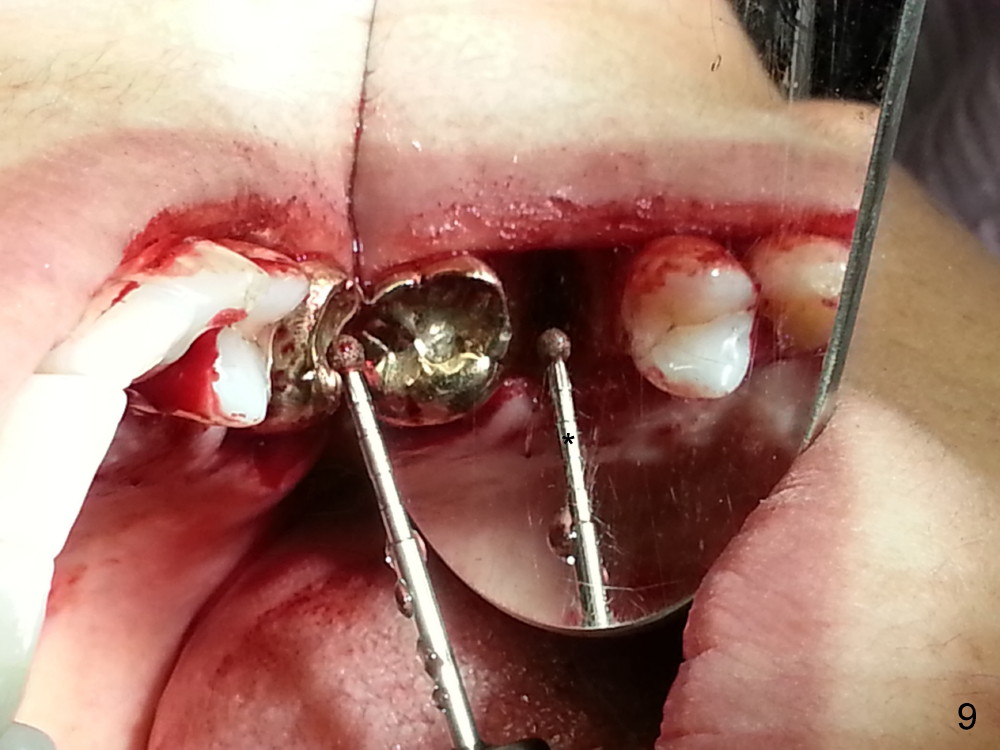

The tooth #13 appears to be affected by periodontits and occlusal trauma (Fig.1*). After using a periotome (Fig.2), the tooth is extracted (Fig.3). The buccal flap is raised (Fig.4). Gingival graft is to be harvested from the site of #15 (Fig.5). The tissue is elevated buccally (Fig.6) and separated (Fig.7). The donor site is covered by a collagen membrane (Fig.8*). A diamond bur is used to induce bleeding from the socket (Fig.9*). Osteotomy is initiated (Fig.10) and enlarged (Fig.11,12). A tapered implant is being placed (Fig.13-15) following internal sinus lift (Fig.16,17). The implant is placed subcrestally, followed by bone graft (Fig.18), soft tissue graft (Fig.19), and suturing (Fig.20 <, Fig.21).